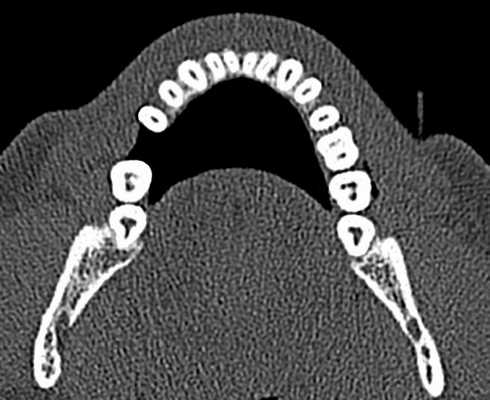

КЛКТ проводилась в лаборатории на аппарате 3D Accuitomo 170. (3D Accuitomo; J. Morita Mfg. Corp., Kyoto, Япония) с плоско-панельным датчиком; область исследования (FOV) — 4×4 см, размер вокселя — 0,16 мм, параметр излучения — 80 кВт, 4мА, 30,8 с.

ВТК зуба 50—150 мкм. а — корень зуба; б — аксиальный срез КЛКТ; в — фрагмент среза данных микроскопии.

Данные КЛКТ, соответствовавшие полученным срезам, выделяли для последующей оценки. Изображения этих участков были представлены в презентации PowerPoint и оценивались 5 врачами, не участвовавшими в подготовке образцов. Для оценки была предложена трехбалльная шкала: 0 — трещина отсутствует; 1 — наличие трещины под сомнением; 2 — трещина имеется.